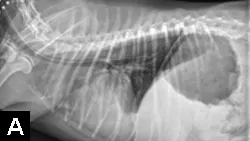

Another quick way to assess placement is to attach the tube end to an airway gas analyzer (eg, capnograph). When the tube end is located in the esophagus or stomach, there is no capnographic waveform, respiratory rate, or end-tidal CO2 detectable by the machine, which sets off its apnea alarm.6 End-tidal CO2 and respiratory rate are both measureable, and a capnographic wave-form is elicited if the tube end is in the trachea, nasopharynx, or nasal cavity. Because an NE or NG tube could be coiled in the nasopharynx (Figure 3) or kinked and still terminate in the esophagus or stomach, survey or contrast radiography is recommended to verify placement. Use of a hyperosmolar, ionic iodinated contrast medium (eg, diatrizoic acid [Hypaque]) should be avoided, as its use in a tube improperly placed in the lungs can result in inflammatory reactions and pulmonary edema.

Although this tube terminates in the esophagus, tube coiling in the nasopharynx and oropharynx will likely cause coughing or vomiting and subsequent oral expulsion of the tube end.